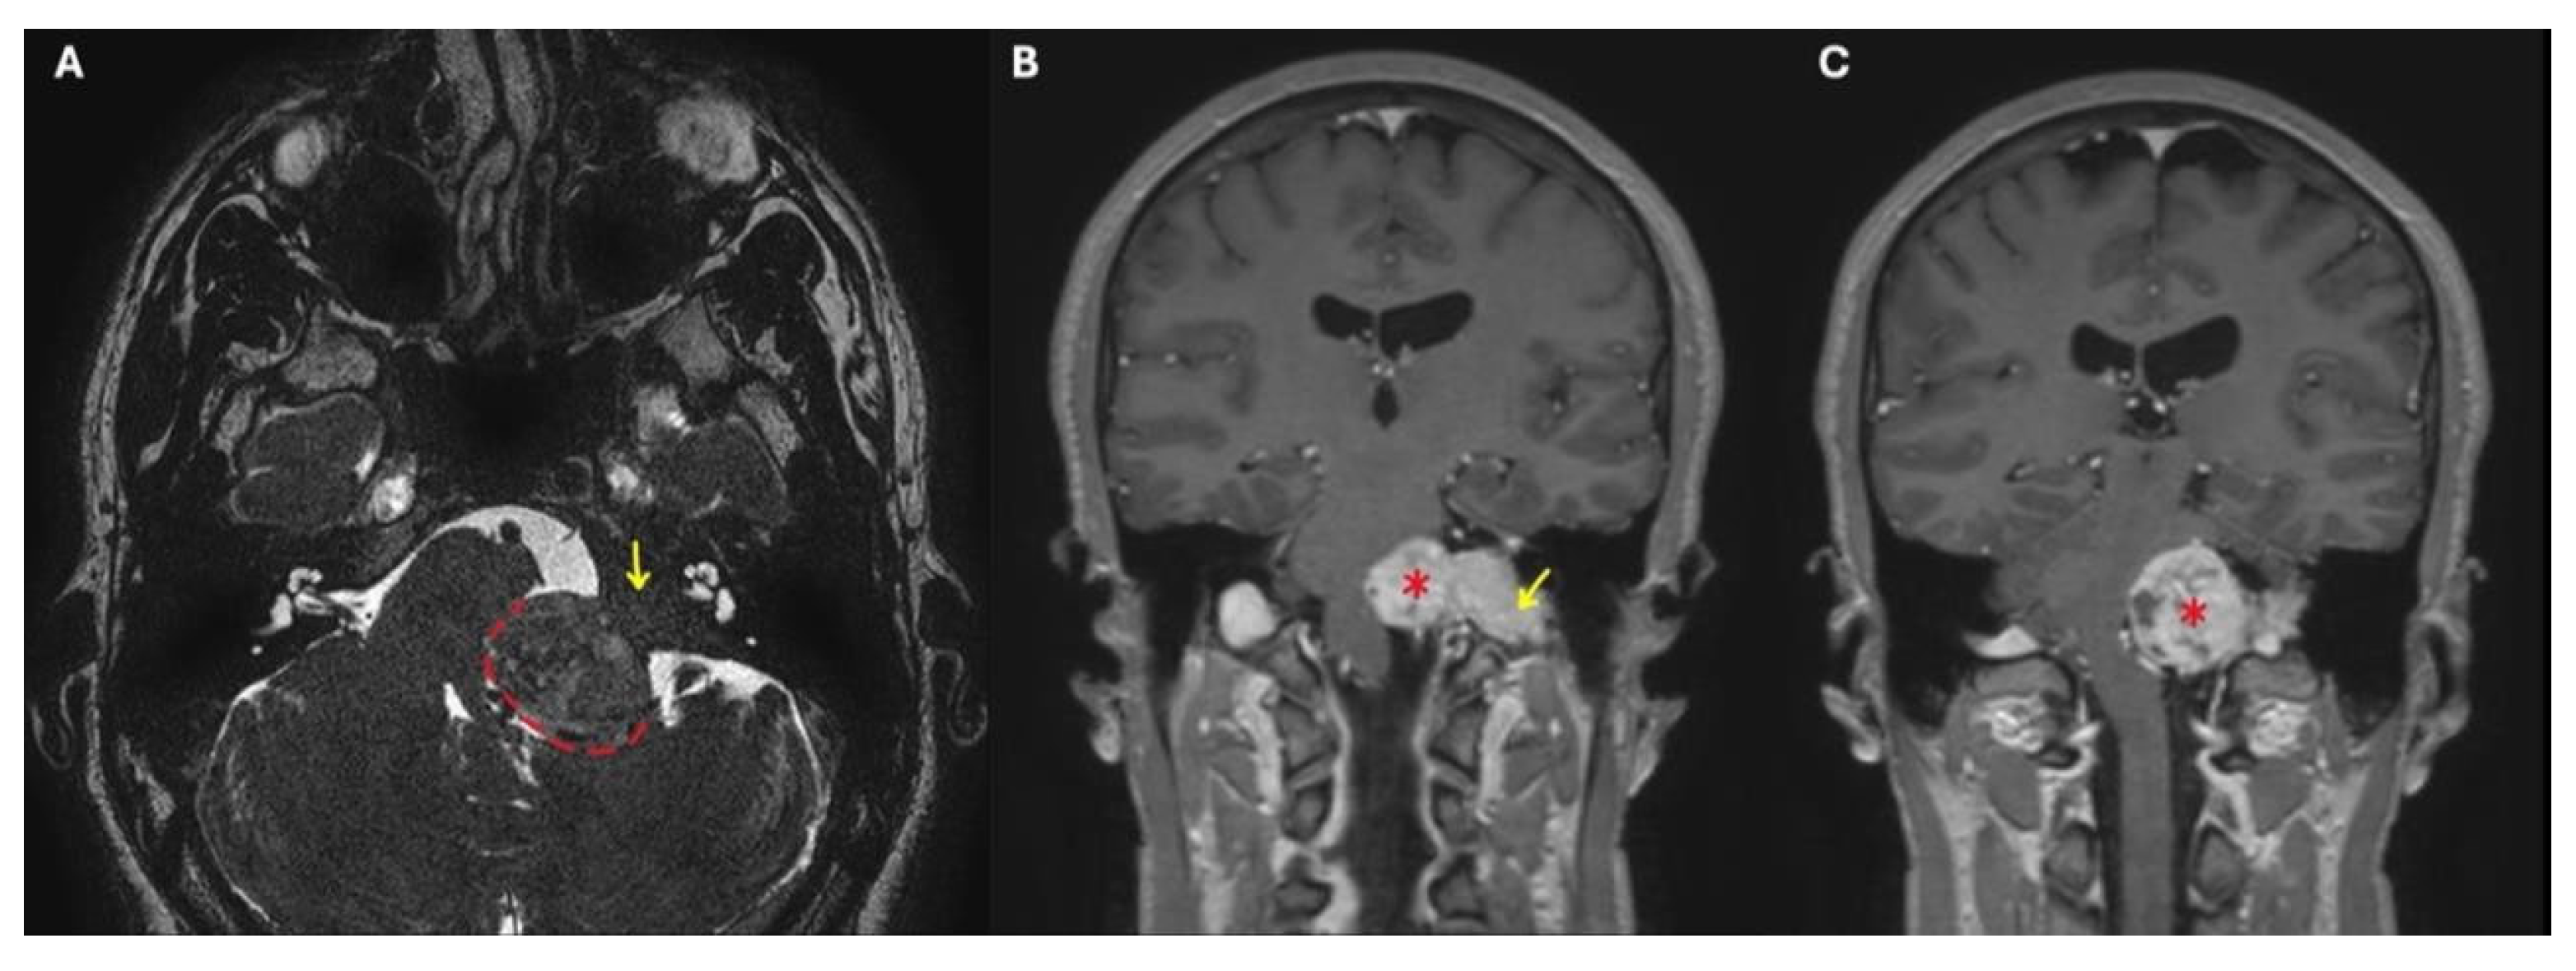

Figure 1. Brain and cerebellopontine-angle MRI of a TJ-PG Di2 class. (A): T2-weighted image; (B) and (C): T1-weighted images with contrast enhancement. *: intradural portion of the TJ-PG Di2; dashed line: brainstem compression by the TJ-PG Di2 in the cisterna magna; yellow arrow: extradural portion of the TJ-PG Di2.

Fisch classified TJ-PGs as types A-D in order of increasing disease extent. This classification considers that up to 20% of these tumors may develop intracranial extension and that their progression can be extradural or intradural. In the latter case, tumors with ≤2 cm of intradural growth are defined as Di1 lesions, while those with a >2 cm extension are called Di2 (Figure 1) [2].

Preoperative angiography has played a vital role in allowing these kinds of large surgical resections, since it gives information concerning the vascularity of the tumor, and the involvement of the internal carotid artery (ICA) and the tumor-feeding vessels, also allowing for their selective embolization. Balloon occlusion testing can inform the risk of stroke should the ICA be sacrificed during the procedure, and an endovascular stent in a tumor-involved vertical petrous ICA can be placed for safer tumor dissection from the vessel walls (Figure 2) [6].